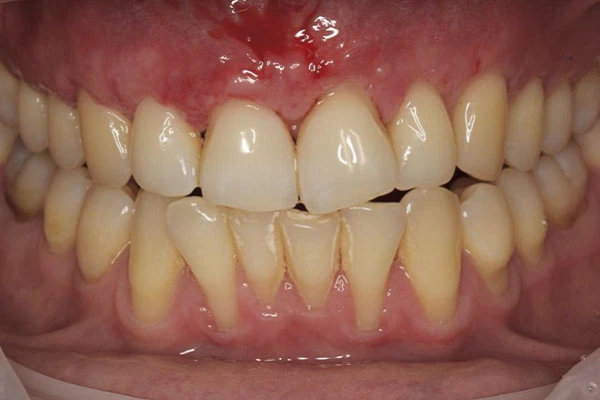

Пластика десен (гингивопластика) - хирургическая коррекция дефектов десен, восстановление и изменение десневого контура. Вмешательство проводится под местной анестезией и позволяет решить как медицинские вопросы, так и вопросы эстетики.

- рецессии (оголение корня зуба)

- неровный, несимметричный десневой контур (десна на разных зубах находится на разных уровнях)

- гипертрофия десны (“акулья улыбка”)